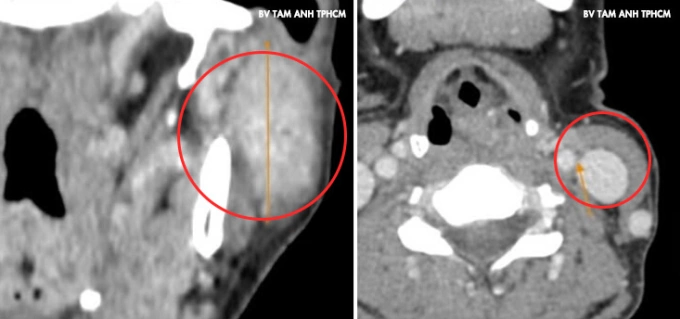

U xuất hiện ở góc hàm mang tai trái của chị Dương một năm trước,nhỏ và không đau,không liệt mặt,khác với đặc điểm chung của loại u này là thường phát triển rất nhanh gây đau và liệt dây thần kinh mặt. Gần đây,u sưng hơn khiến mặt mất cân đối,chị đến Phòng khám Đa khoa Tâm Anh Quận 7 kiểm tra. Kết quả chụp CT và siêu âm ghi nhận khối u dài hơn 4 cm chiếm gần hết mô tuyến mang tai trái,phát triển vào trong xâm lấn dây thần kinh 7 và tĩnh mạch sau hàm. Cạnh trước khối u có hạch gần 1 cm và hai hạch hơn 1 cm vùng cổ. Kết quả sinh thiết chọc hút tế bào kim nhỏ là u tuyến mang tai hóa bọc,chưa xác định ung thư.

Ảnh chụp CT ghi nhận khối u lớn vùng mang tai trái của chị Dương. Ảnh: Bệnh viện Đa khoa Tâm Anh